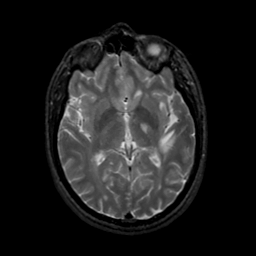

MR Study #22, December 1, 1991 -- Slice #25

[Home][Help][Clinical][Tour 1][Tour 2] Slice 25